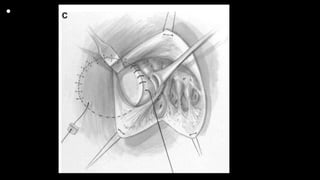

• Figures 1 and 2 Standard cardiopulmonary bypass with direct

bicaval cannulation is achieved, even in the neonate, at

a systemic temperature of 28°C to 32°C (cannulas removed for

clarity). A vent is placed through the right superior

pulmonary vein and cold blood cardioplegia administered after

aortic cross clamping. A right atriotomy is made parallel

and close to the right atrioventricular groove. Placing the incision

in this location assists in the exposure by elevating the

anterior wall of the right ventricle and tricuspid valve with the

stay sutures inserted along the atriotomy. The ventricular

septal defect is visible behind the anterior leaflet of the tricuspid

valve. Traction sutures are placed in the anterior and

septal leaflets of the tricuspid valve. In the neonate, a patent

foramen ovale is generally left open, but is closed in older

infants

Figure 3 The traction sutures placed on the anterior and septal leaflets of the tricuspid

valve are essential in providing

exposure with minimal retractors in the field. Each suture is retracted directly toward

the surgeon, which pulls the

septum and VSD into view. A small right-angle retractor is then placed under the

anterior leaflet and pulled superiorly.

The anterior limb of the septal band is identified. A traction suture placed here can

help in the visualization of the out

flow tract and help in keeping the surgeon’s orientation. The traction suture placed in

the anterior limb of the septal

band, which marks the anterior edge of the VSD, can be very helpful in maintaining

orientation and exposing the distal

outflow tract. Anterior and superior to this point is the pathway to the pulmonary

valve, and the marking suture serves

as a useful frame of reference to avoid an incision into the VSD itself